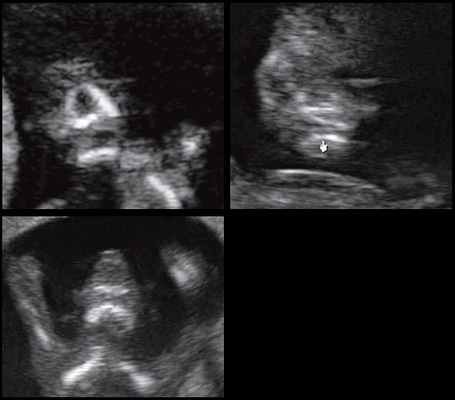

Пренатальная УЗИ черепно-лицевых аномалий плода

Пренатальная диагностика черепно-лицевых аномалий является важным и обязательным аспектом, так как аномалии этих структур могут указывать на наличие других, более тонких аномалий, синдромов, хромосомных мутаций или даже более редких состояний, таких как инфекции или нарушения обмена веществ.

Она остается сложным процессом, особенно в первом триместре. Частота выявления черепно-лицевых аномалий(ЧЛА) варьируется в зависимости от типа аномалии, ее тяжести, гестационного возраста, сопутствующих аномалий, а также методов и технологий ультразвуковых исследований. Так распространенность хейлосхизиса и краниосиностоза составляет около 0,15% и 0,05% соответственно.

Изменения мозгового отдела черепа

Размер, форму, целостность и плотность кости черепа можно оценить, когда измеряется размер головы и когда исследуются структуры головного мозга. Череп имеет овальную форму и непрерывную эхогенную структуру, прерываемую только узкими эхолуцентрическими швами. Аномальные особенности (Рис. 1-3) и связанные с ними аномалии показаны в Таблице 1.

Диагностика краниосиностоза выражается в потере гипоэхогенности в сегменте основных швов черепа, вместе с расширением других ортогональных швов. Косвенные признаки, включая аномальный цефальный индекс (ЦИ), форму черепа (Таблица 2) и/или морфологию лица, такую как гипотелоризм или гипертелоризм, могут предшествовать закрытию швов на 4-16 неделе. ЦИ ниже 70% или выше 85% указывают на долихоцефалию и брахицефалию соответственно.

3D/4D объемная визуализация

Использование трехмерного ультразвука, включая визуализацию поверхности, многоплоскостное и многослойное изображение, позволяет точно оценить различные черепно-лицевые структуры и их аномалии, включая расщелину неба (рис. 15, 16) и краниосиностоз. Изображения могут быть полезны для консультирования (рис. 17, 18). Использование 3D (рис. 19) может помочь дифференцировать закрытые и открытые швы. Использование 4D может быть использовано для оценки выражений лица.

Рисунок 19: Плод во втором триместре с краниосиностозом.

3D поверхностное изображение в скелетном режиме, аксиального вида черепа показывает сужение (стрелки) венечного шва (CS) и части переднего родничка (AF).